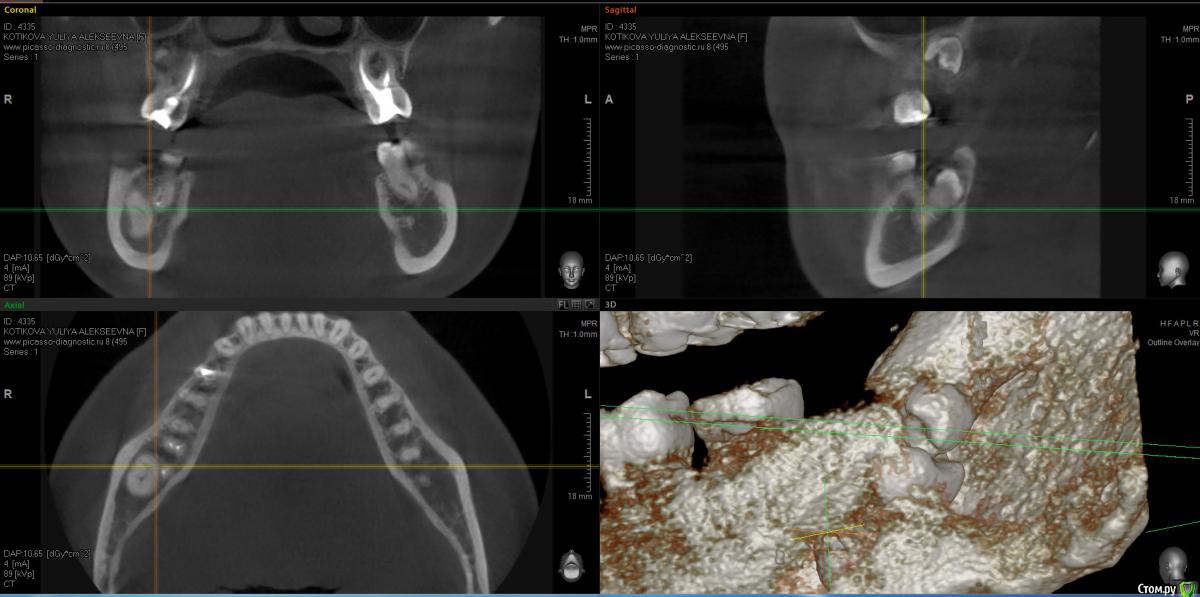

Kitten Опубликовано 20 декабря, 2014 Автор Поделиться Опубликовано 20 декабря, 2014 Я сделала ОПТГ и КТ. Ссылка на КТ ниже. Для тех, у кого нет возможности скачать файл полностью, приложила скриншоты. Жду ваши рекомендации. https://yadi.sk/d/3-GC2npldVBv4 Ссылка на комментарий

red_butler Опубликовано 20 декабря, 2014 Поделиться Опубликовано 20 декабря, 2014 ищите специалиста и в путь, форум Вам в помощь 2 Ссылка на комментарий